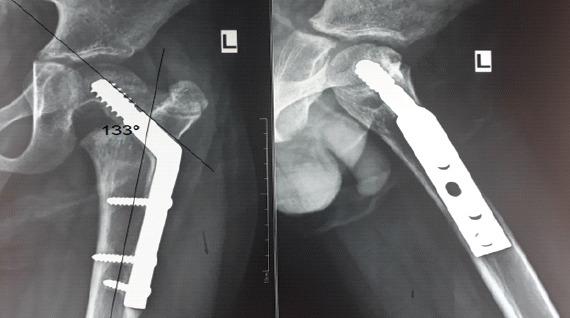

A 7-year-old boy with left hip pain presented without any history of trauma or systemic illness. Radiographs and computed tomography imaging revealed coxa vara with a transcervical femoral neck fracture with a mixed predominantly sclerotic lesion in the femoral neck. A closed-wedge valgus osteotomy was performed with internal fixation using a locking plate and screws placed proximal to the physis. Intraoperative biopsy ruled out tumor or infection. Although initial outcomes were favorable, recurrence of coxa vara and femoral neck fracture occurred after 1 year and 9 months. Revision surgery involved medial open-wedge osteotomy with bone grafting and fixation using a pediatric dynamic hip screw, with the lag screw crossing the physis for stability. At the 8th-year follow-up, the patient was pain-free, with minimal limb shortening and good functional mobility. X-rays showed solid radiographic union, disappearance of the previously noted sclerotic lesion in the left femoral neck, and maintenance of the NSA.

This case involves coxa vara with atypical radiographic features, complicating its classification as developmental or acquired. Initial fixation that preserved the physis resulted in recurrence. Subsequent fixation crossing the physis, along with correction of the Hilgenreiner epiphyseal (HE) angle, effectively prevented recurrence. At 8-year follow-up, the patient demonstrated a good clinical and radiological outcome.

The HE angle is a critical prognostic factor in predicting the recurrence of coxa vara. Surgical stability should take precedence over physeal preservation.

一名7岁男孩因左髋疼痛就诊,无任何外伤或全身疾病史。X线片和计算机断层扫描成像显示髋内翻合并经颈股骨颈骨折,股骨颈有一个以硬化为主的混合性病变。采用闭合楔形外翻截骨术,使用锁定钢板和螺钉在骨骺近端进行内固定。术中活检排除肿瘤或感染。尽管初始结果良好,但1年9个月后髋内翻和股骨颈骨折复发。翻修手术采用内侧开放楔形截骨术并植骨,并使用儿童动力髋螺钉固定,拉力螺钉穿过骨骺以确保稳定。在第8年随访时,患者无疼痛,肢体缩短最小,功能活动良好。X线片显示骨折牢固愈合,左侧股骨颈先前 noted的硬化病变消失,NSA维持正常。

本病例涉及具有非典型放射学特征的髋内翻,使其难以分类为发育性或后天性。最初保留骨骺的固定导致复发。随后穿过骨骺的固定,以及对希尔根赖纳骨骺(HE)角的矫正,有效防止了复发。在8年随访时,患者显示出良好的临床和放射学结果。

HE角是预测髋内翻复发的关键预后因素。手术稳定性应优先于骨骺保留。